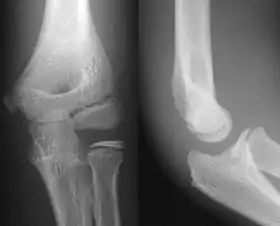

- Elbow - AP and Lateral. Radial head projections available on request

- Knee - AP and Lateral. Intra Condular projections on request

Right knee, anteroposterior

Right knee, lateral